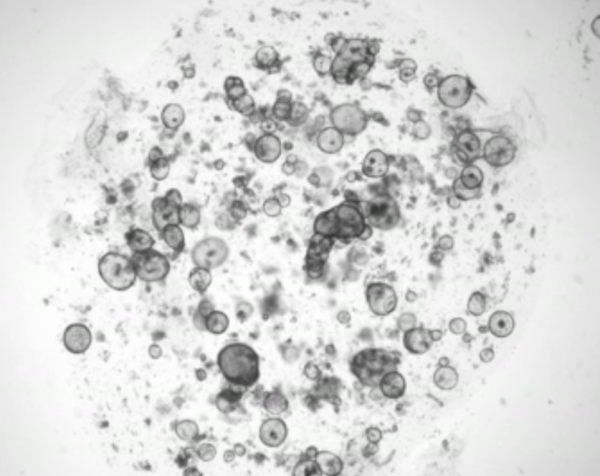

小鼠泪腺类器官共聚焦显微照片。图中泪液产物Lcn2标记为红色,表明这些类器官正在分泌泪液。图片来源:Yorick Post, Hubrecht Institute

为了克服这一障碍,研究人员采用先前用于其他器官的方法,构建了来源于成体干细胞的小鼠和人类泪腺3D类器官。类器官可以持续生长数月,并能够重现分泌大部分泪液的泪腺上皮组织在结构、转录和功能方面的特征。值得注意的是,如果暴露在能刺激泪液分泌的神经递质——去甲肾上腺素中,这些类器官也会像气球一样膨胀起来。